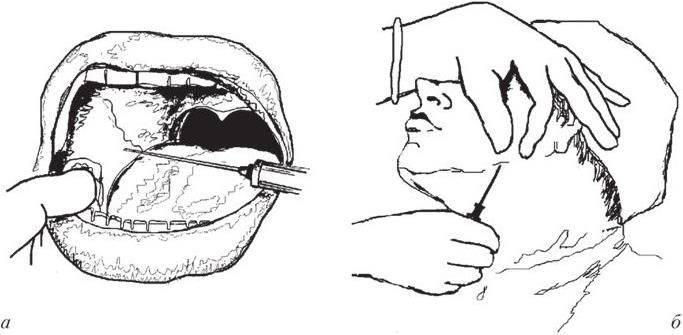

Внутриротовой доступ: обезболивание может быть проведено аподактильно или после предварительного ощупывания костных анатомических ориентиров. Анестезию после предварительного ощупывания начинают с пальпаторного определения позадимолярной ямки и височного гребешка, который и является ориентиром для вкола иглы. При широко открытом рте инъектор располагают на уровне премоляров противоположной стороны и вкалывают иглу кнутри от височного гребешка на 0,7 – 1,0 см выше поверхности смыкания близстоящего зуба, продвигая ее кнаружи и кзади до соприкосновения с костью. Выводят часть анестезирующего раствора, чем достигают блокирования язычного нерва. Продвинув иглу вглубь еще на 2 см и достигнув костного желобка, вводят оставшуюся часть раствора анестетика, блокируя нижний луночковый нерв (рис. 1.6, а).

Рис. 1.6. Обезболивание нижнелуночкового нерва у нижнечелюстного отверстия:

а – внутриротовой доступ; б – внеротовой доступ

При выполнении анестезии подчелюстным доступом иглу вкалывают в кожу под внутреннюю поверхность нижнего края челюсти, отступя на 1,5 см от угла, и продвигают ее по кости параллельно заднему краю ветви на 3,5 – 4 см. Здесь создают депо анестезирующего раствора в количестве 1 мл, чем обеспечивают блокирование нижнего луночкового нерва. Затем, продвинув иглу еще на 1 см, вводят 1 мл анестетика, выключая щечный и язычный нервы. При продвижении иглы на 4 см от нижнего края челюсти и введении в ткань анестезирующего раствора обычно не возникает необходимость в дополнительном перемещении иглы к язычному и щечному нервам, так как диффузия раствора обеспечивает обезболивание в зоне иннервации всех трех нервов (рис. 1.6, б). При проведении анестезии по изложенному способу у больных с короткой шеей следует вкалывать иглу без шприца, так как он мешает продвижению иглы по кости. Шприц присоединяют к игле, достигнув уровня нижнёчелюстного отверстия.